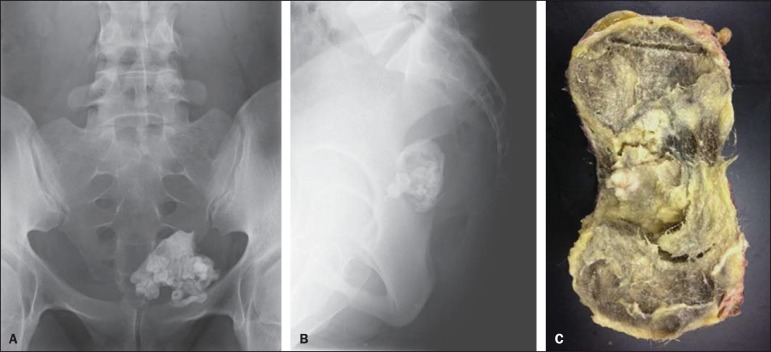

В 2015 году в Бразилии 25-летняя женщина обратилась к врачу с жалобами на боль в нижней части спины, мучившую ее уже два месяца. Первичный осмотр не выявил никаких патологий, в вот УЗИ органов таза показало крупное, 10,3×9,2×8,6 см, образование в области яичника.

После удаления врачи установили, что оно состояло в основном из жировой ткани, но также в опухоли содержались волосы и зубы.

Зубы — не редкость для тератом яичника, они обнаруживаются более чем в трети случаев. Периодически они попадаются даже в археологических находках — так, фрагменты новообразования были найдены среди тазовых костей женщины древнеримской эпохи в Испании. В небольшом шарике среди тазовых костей древней римлянки оказались четыре зуба и кусок кости.